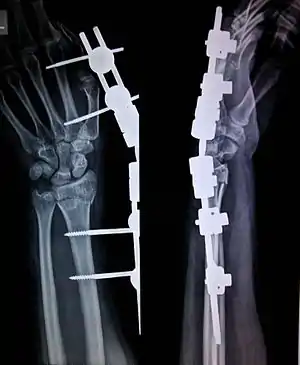

External fixation is a surgical treatment wherein rods are screwed into bone and exit the body to be attached to a stabilizing structure on the outside of the body.[1] It is an alternative to internal fixation, where the components used to provide stability are positioned entirely within the patient's body. It is used to stabilize bone and soft tissues at a distance from the operative or injury focus. They provide unobstructed access to the relevant skeletal and soft tissue structures for their initial assessment and also for secondary interventions needed to restore bony continuity and a functional soft tissue cover.

In this kind of reduction, holes are drilled into uninjured areas of bones around the fracture and special bolts or wires are screwed into the holes. Outside the body, a rod or a curved piece of metal with special ball-and-socket joints joins the bolts to make a rigid support. The fracture can be set in the proper anatomical configuration by adjusting the ball-and-socket joints. Since the bolts pierce the skin, proper cleaning to prevent infection at the site of surgery must be performed.

The parts of an external fixator include:

- Schanz pin

- Connecting rods

- Clamps